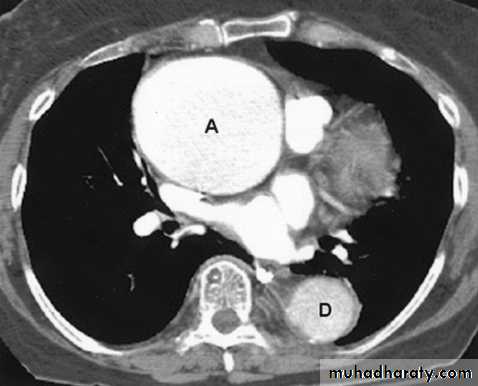

Aortic aneurysm : Dilatation of the ascending aorta may be due to aneurysm

formation or secondary to aortic regurgitation, aortic stenosis or systemic hypertension.

Substantial dilatation of the ascending aorta is needed before a bulge of the right mediastinal border can be recognized.

aortic unfolding is a commoner cause of a bulge of the right superior mediastinum than ascending aortic aneurysm.

The two common causes of aneurysm of the descending aorta are atheroma and aortic dissection.

Computed tomography with intravenous contrast enhancement, magnetic resonance angiography (MRA) and/or echocardiography are very useful when aortic aneurysms are assessed .

Aortic dissections can be shown with CT (and MRI) and these non-invasive techniques have, in practice, replaced aortography.

Aortic aneurysm

Aortic dissection